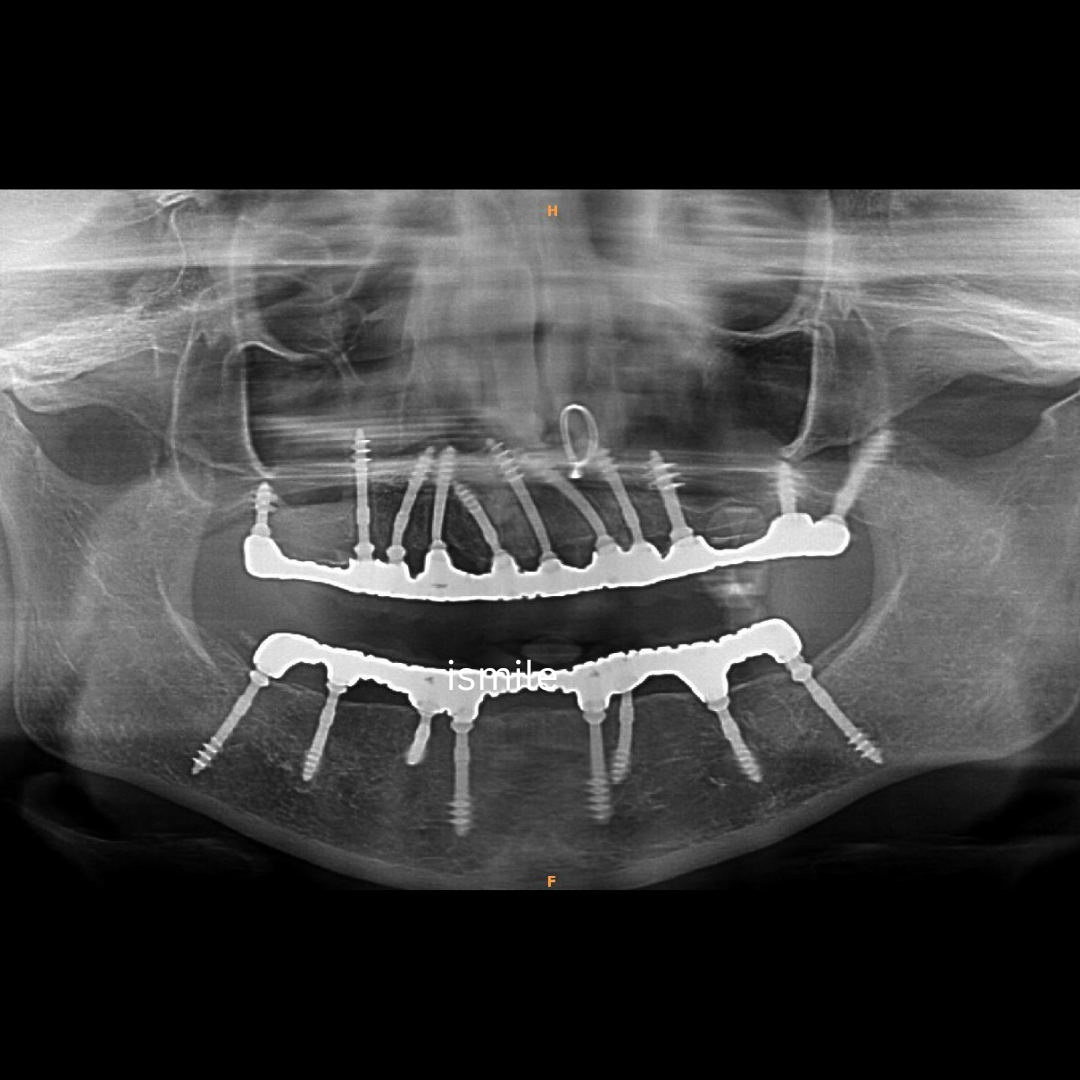

Cortical Implants

Cortical implants are advanced dental implants that anchor directly into the strong cortical bone, allowing immediate stability and faster tooth replacement even in patients with low bone density. Know More

Traditional Implants Vs Cortical (Basal) Implants

| Comparison Factor | Traditional Implants | Cortical (Basal) Implants |

|---|---|---|

| Bone Anchorage | Placed in Cancellous (spongy) bone. | Placed in Cortical (dense/hard) bone. |

| Time to Final Teeth | 3 to 6 months (requires healing time). | Immediate Loading (72 Hours). |

| Bone Grafting | Often needed if bone density is low. | Rarely needed; uses existing deep bone. |

| Surgical Stages | Two-stage surgery is common. | Single-stage (often flapless/minimally invasive). |

| Risk of Infection | Susceptible to Peri-implantitis in spongy bone. | Highly resistant to infection due to smooth surface. |

| Ideal For | Single tooth with healthy bone. | Full mouth restoration & "no-bone" cases. |